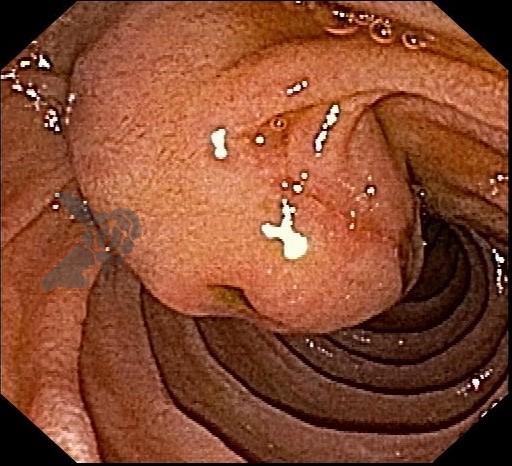

Figuras 1 e 2. Imagem endoscópica em visão direta de lesão protrusa entre pequena curvatura e parede posterior de corpo gástrico proximal, revestida por mucosa com superfície regular, normocorada e íntegra. A imagem ecoendoscópica demonstra lesão com ecogenicidade hipoecoica, ecotextura homogênea, formato ovalado, sem características internas, sem vascularização ao doppler, limites precisos, contornos regulares, medindo aproximadamente 20 x 6 mm e inserida em camada muscular própria. Punções ecoguiadas foram realizadas com agulha FNB, sendo o anatomopatológico e imuno-histoquímica compatíveis com GIST gástrico. Fonte: arquivos do Instituto do Câncer do Estado de São Paulo (ICESP/HCFMUSP)Figuras 1 e 2. Imagem endoscópica em visão direta de lesão protrusa entre pequena curvatura e parede posterior de corpo gástrico proximal, revestida por mucosa com superfície regular, normocorada e íntegra. A imagem ecoendoscópica demonstra lesão com ecogenicidade hipoecoica, ecotextura homogênea, formato ovalado, sem características internas, sem vascularização ao doppler, limites precisos, contornos regulares, medindo aproximadamente 20 x 6 mm e inserida em camada muscular própria. Punções ecoguiadas foram realizadas com agulha FNB, sendo o anatomopatológico e imuno-histoquímica compatíveis com GIST gástrico. Fonte: arquivos do Instituto do Câncer do Estado de São Paulo (ICESP/HCFMUSP)Figuras 3 e 4. Imagem endoscópica em visão direta de abaulamento de parede em segunda porção duodenal distalmente à papila duodenal maior, revestida por mucosa com íntegra, de coloração amarelada e superfície regular. A ecoendoscopia demonstra lesão com ecogenicidade hiperecoica, ecotextura homogênea, formato arredondado, medindo cerca de 10 mm no maior eixo, com limites precisos, contornos regulares, medindo cerca de 10 mm no maior diâmetro e inserida em camada submucosa, sendo os achados endoscópicos e ecoendoscópicos compatíveis com lipoma.Figuras 3 e 4. Imagem endoscópica em visão direta de abaulamento de parede em segunda porção duodenal distalmente à papila duodenal maior, revestida por mucosa com íntegra, de coloração amarelada e superfície regular. A ecoendoscopia demonstra lesão com ecogenicidade hiperecoica, ecotextura homogênea, formato arredondado, medindo cerca de 10 mm no maior eixo, com limites precisos, contornos regulares, medindo cerca de 10 mm no maior diâmetro e inserida em camada submucosa, sendo os achados endoscópicos e ecoendoscópicos compatíveis com lipoma.Fig. 5. Imagem endoscópica em visão direta de lesão protrusa em parede anterior de antro gástrico proximal, revestida por mucosa normocorada, com superfície regular, sendo sugestiva de lesão subepitelial.Fig. 6. A ecoendoscopia evidencia lesão com ecogenicidade hipoecoica, ecotextura predominantemente homogênea, formato arredondado, limites precisos, bordos regulares, medindo aproximadamente 13,4 x 12 mm, sem focos hiperecoicos ou calcificações no interior e inserida na camada muscular própria. Punções ecoguiadas foram realizadas com agulha FNB, sendo anatomopatológico e imuno-histoquímica confirmando schwanomma gástrico.Fig. 7 e 8. Imagem de esofagogastroduodenoscopia demonstra lesão protrusa em papila duodenal maior revestida por mucosa enantemática e com superfície com três erosões recobertas por fibrina.Fig. 7 e 8. Imagem de esofagogastroduodenoscopia demonstra lesão protrusa em papila duodenal maior revestida por mucosa enantemática e com superfície com três erosões recobertas por fibrina.Fig. 9 e 10. Imagem à ecoendoscopia demonstra lesão com formato ovalado, ecogenicidade hipoecoica, ecotextura heterogênea, com contornos regulares, sem adenopatia adjacente, sem vascularização ao doppler, sem características internas, medindo cerca de 20 x 11 x 24 mm, inserida na camada submucosa, não havendo acometimento da muscular própria. Foram realizadas punções ecoguiadas com agulha FNA 22 gauge, sendo o anatomopatológico e imunohistoquímica compatíveis com tumor neuroendócrino de papila duodenal bem diferenciado grau 1.Fig. 9 e 10. Imagem à ecoendoscopia demonstra lesão com formato ovalado, ecogenicidade hipoecoica, ecotextura heterogênea, com contornos regulares, sem adenopatia adjacente, sem vascularização ao doppler, sem características internas, medindo cerca de 20 x 11 x 24 mm, inserida na camada submucosa, não havendo acometimento da muscular própria. Foram realizadas punções ecoguiadas com agulha FNA 22 gauge, sendo o anatomopatológico e imunohistoquímica compatíveis com tumor neuroendócrino de papila duodenal bem diferenciado grau 1.Fig. 11 e 12. Esofagogastroduodenoscopia demonstra abaulamento de parede anterior de corpo gástrico proximal, com mucosa normocorada, superfície regular com depressão central, sendo compatível com lesão subepitelialFig. 11 e 12. Esofagogastroduodenoscopia demonstra abaulamento de parede anterior de corpo gástrico proximal, com mucosa normocorada, superfície regular com depressão central, sendo compatível com lesão subepitelialFig. 13 e 14. Ecoendoscopia demonstrou formação com ecogenicidade hipoecoica, ecotextura homogênea, formato ovalado, limites bem definidos, contornos regulares, medindo aproximadamente 13 mm e inserida na camada submucosa. Lesão foi submetida a ressecção endoscópica transmural com dispositivo FTRD. A histopatologia e imunohistoquímica confirmaram TNE gástrico bem diferenciado grau 2.Fig. 13 e 14. Ecoendoscopia demonstrou formação com ecogenicidade hipoecoica, ecotextura homogênea, formato ovalado, limites bem definidos, contornos regulares, medindo aproximadamente 13 mm e inserida na camada submucosa. Lesão foi submetida a ressecção endoscópica transmural com dispositivo FTRD. A histopatologia e imunohistoquímica confirmaram TNE gástrico bem diferenciado grau 2.